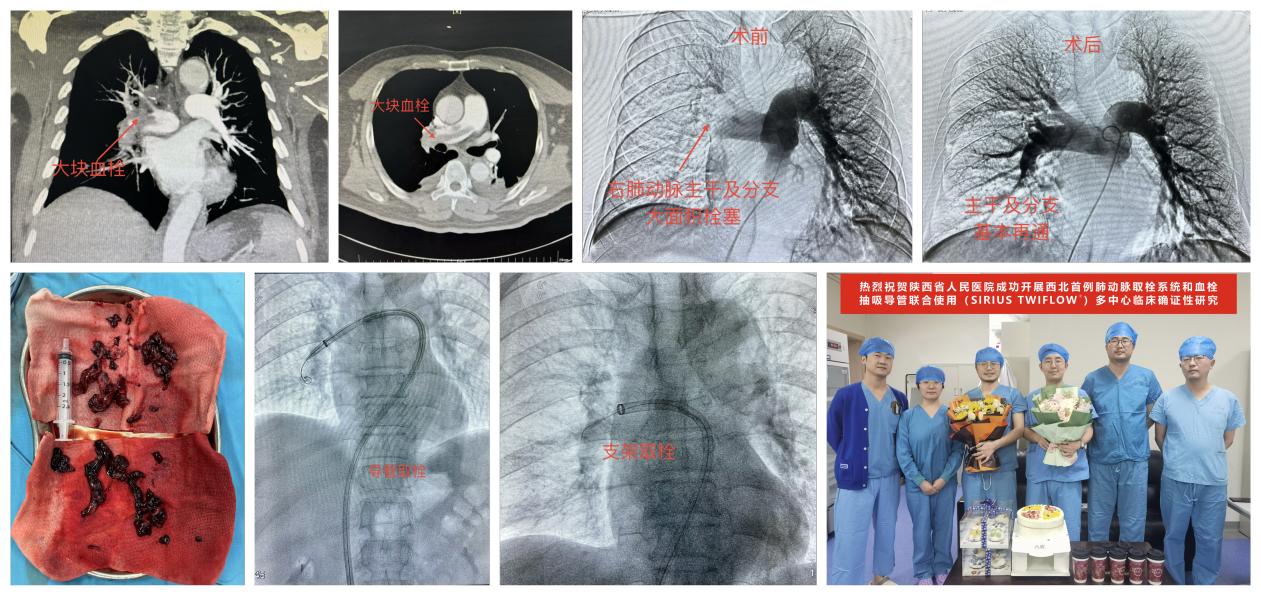

近日,心血管内二科寿锡凌主任领衔,由介入放射科实施,采用SIRIUS TWIFLOW®肺动脉取栓系统与血栓抽吸导管成功为1例急性肺栓塞患者完成了肺动脉血栓清除手术,作用显著,术后肺动脉压力从40/11mmHg下降至30/9mmHg,胸闷、气短症状明显缓解,随即脱离呼吸机。此次手术的顺利完成标志着“SIRIUS TWIFLOW®肺动脉取栓系统与血栓抽吸导管联合使用”全国多中心确证性临床研究在西北地区正式拉开序幕。

患者为中年男性,左腿外伤术后1周,半天前突发性胸闷、气短、大汗淋漓等症状,面罩吸氧不能缓解,行肺动脉CTA提示肺动脉主干及右肺动脉大面积栓塞。经心内二科寿锡凌主任、重症医学科宗媛主任、王婵医师及介入科陈思攀医师多学科讨论后认为,患者肺栓塞诊断明确,病情危重,且近期有外科手术史,单纯抗凝治疗作用不佳,经外周静脉溶栓起效慢、出血风险大,遂决定由介入科进行肺动脉取栓术,以期在最短时间内减轻血栓负荷,恢复肺动脉血流,降低右心功能衰竭风险。手术医生运用新型血栓抽吸导管及取栓支架,顺利将肺动脉主干及分支内绝大部分血栓取出,术后即刻患者自觉胸闷气短症状明显缓解,并脱离呼吸机辅助呼吸,改为鼻导管吸氧。

心内二科寿锡凌主任团队一直致力于急危重症心肺疾病的诊治,此次采用新型肺动脉取栓系统对高危肺栓塞患者成功救治,是团队作为该研究项目的西北唯一临床实验分中心的首例,同时也标志着团队对于急危重症肺栓塞救治实力的进一步增强,今后能更好地为三秦父老提供高效安全的医疗服务。